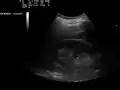

The hepatorenal recess[1] (subhepatic recess, pouch of Morison or Morison's pouch) is the subhepatic space that separates the liver from the right kidney. As a potential space, the recess is not normally filled with fluid. However, fluid can collect here in circumstances where the abdomen fills with fluid, such as hemoperitoneum. This fluid may be seen on ultrasound or computed tomography (CT scan).

Since it is a potential space, the hepatorenal recess is not normally filled with fluid. However, this space becomes significant in conditions in which fluid collects within the abdomen (most commonly ascites and hemoperitoneum). The intraperitoneal fluid, be it blood, ascites, or dialysate, collects in this space and may be visualized, most commonly via ultrasound or computed tomography (CT) scanning. As little as 30 or 40 ml of fluid in the abdominal cavity may be visualized in this space.

Early visualization of fluid in the hepatorenal recess on FAST scan may be an indication for urgent laparotomy.[2]